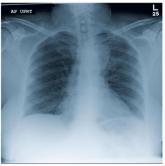

A 63-year-old woman presents to your clinic with complaints of general malaise, weakness, and occasional cough—symptoms that started a couple of days ...